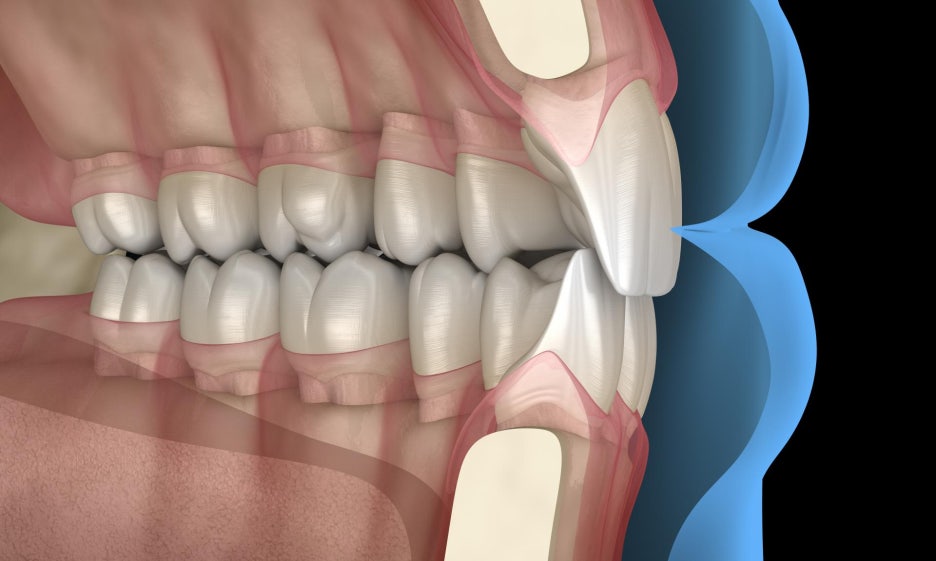

보철 제작 시 고려해야 될 spee, wilson 만곡

자연치가 상실되었을 때

잃어버린 기능과 외관을 살려주는 인공치,

이때 크라운이 예쁘게 잘 만들어졌는지도 중요하지만

올바른 교합 이 형성되었는지 확인해야 됩니다.

교합 이 알맞지 않은 경우,

즉 위, 아래 치아들이 맞물릴 때

편하지 않고 불편함이 느껴지게 되는데요.

생각보다 큰 문제들이 생기게 됩니다.

음식을 먹을 때는 물론이며

평소 대화를 하거나 생활을 할 때에도

쉴 틈 없이 접촉을 하게 됩니다.

이뿐만 아니라 좀 더 편한 쪽으로

사용을 하기 위해 편측 저작이 생길 수 있으며

추후 턱관절 장애, 안면비대칭으로도 이어질 수 있습니다.

심지어는 교합력이 한쪽으로만 쏠리게 되어

다른 치아들이 파절될 확률도 있죠.